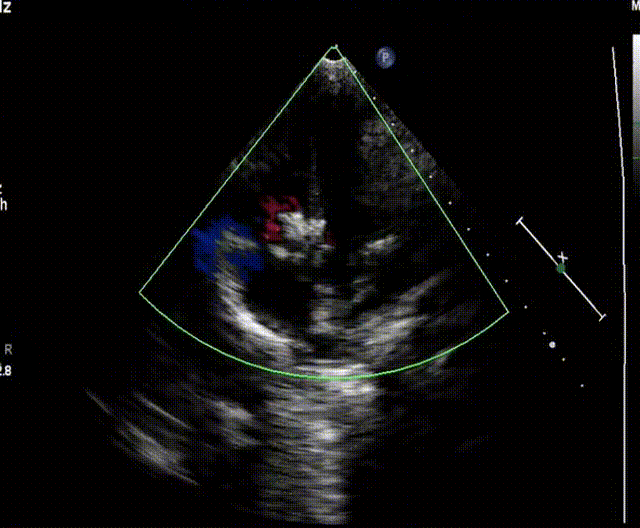

患者为4岁男童,与同龄儿相比左室增大,左房稍增大,右房室与室间隔厚度正常。室间隔上段膨向右室并连续中断,左室长轴观察回声脱失约6mm,两个破口,分流约4mm。二尖瓣形态,结构正常,有轻微返流,主动脉根部内径正常。超声诊断:室间隔瘤形成并缺损(膜部至嵴下混合型),室水平左向右分流。

▲术前超声